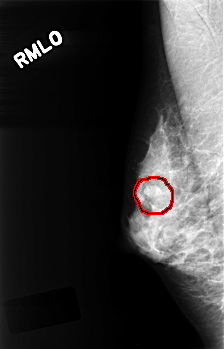

C_0336_1.RIGHT_MLO

RIGHT_MLO LINES 4528 PIXELS_PER_LINE 2912 BITS_PER_PIXEL 12 RESOLUTION 50 OVERLAY

FILE: C_0336_1.RIGHT_MLO.OVERLAY

TOTAL_ABNORMALITIES 1

ABNORMALITY 1

LESION_TYPE MASS SHAPE OVAL MARGINS CIRCUMSCRIBED

ASSESSMENT 4

SUBTLETY 5

PATHOLOGY BENIGN

TOTAL_OUTLINES 1

BOUNDARY